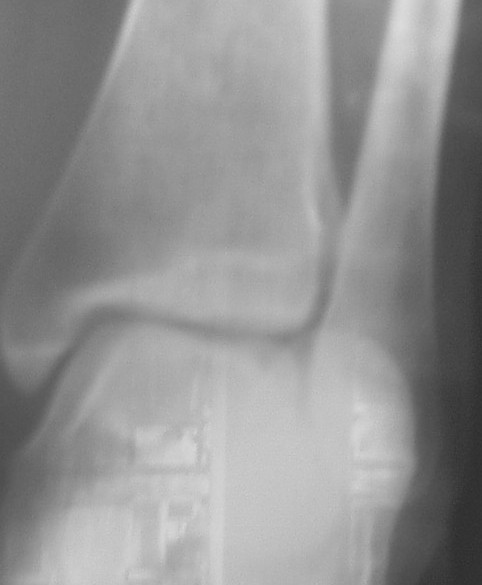

Трехчетвертной

На боковом довольно неплохой сустав, скудная информация о положении вилки сустава при косой рентгенограмме (Mortise view) из-за положения стопы во внутренней ротации и эквинуса во время ренгенограммы.

Мне кажется это тень внутренней лодыжки, которая находится в положении сгибания (flexion), т.е. указывающее на неправильно сросшийся или несросшийся перелом.

На представленных снимках с исправлением, нейтральное положение стопы во время рентгенограммы, укорочение малоберцовой не менее 4-5 мм и ротация, смещенная и ротированная внутренняя лодыжка.